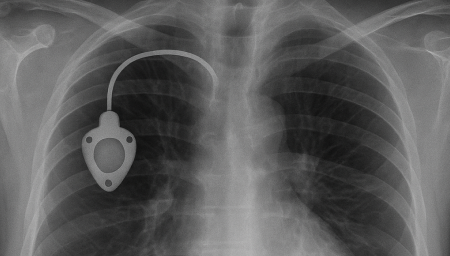

Chemoport는 항암제처럼 자극이 강한 약물을 안전하고 안정적으로 투여하기 위해 흉부 피부 아래에 이식하는 중심정맥 사용 포트입니다. 팔 혈관이 약하거나 반복 주사로 인한 통증이 걱정되는 환자에게 도움을 줄 수 있으며, 장기간 치료가 필요한 경우 편안하게 항암 치료를 지속할 수 있도록 설계되어 있습니다.

항암관(Chemoport)삽입 과정

01

국소마취 후 작은 절개를 시행 (보통 쇄골 아래 약 2~3cm 정도 절개)

02

정맥에 카테터 삽입 후 포트와 연결

03

방사선으로 카테터 위치 확인

04

피부 봉합 후 소독 드레싱